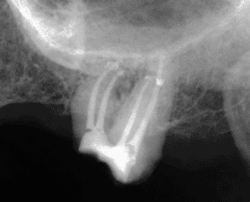

Analytic Autofit Greater Taper Gutta Percha™ (SybronEndo) in tapers .04 and .06 were used for obturation of the root canals. The gutta-percha cones were fit for point tug-back in each canal in the presence of NaOCl and a cone-fit radiograph was taken to verify correct length and fit. Final irrigation of the canals consisted of EDTA liquid, NaOCl, and then 95% ethanol. Analytic Autofit Greater Taper Paper Points™ (SybronEndo) were used to dry the root canals. A thick mix of Kerr Pulp Canal Sealer EWT™ (SDS Kerr) was prepared. A small amount of sealer was then placed on the tip of each master gutta-percha cone prior to being placed into the canal. A warm vertical method of obturation was used. The System B Heat Source™ (SybronEndo) was used for the down-pack according to manufacturer’s instructions. When the heat source was removed, the gutta-percha was then condensed using a Dovgan Plugger™ (Miltex Dental). The canals were then back-filled with gutta-percha using the Obtura II System™ (Obtura Spartan). The larger end of a Dovgan Plugger was then used to vertically condense the gutta-percha at each canal orifice. The coronal access was sealed with a temporary restorative material and post-operative radiographs were then taken (Fig. 5).

Fig. 5: Post-operative radiograph, tooth #15. Conclusion